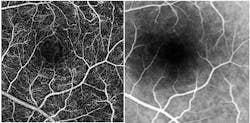

Speaking at the BiOS Hot Topics session during Photonics West 2010, Professor Amiram Grinvald, founder and CEO of Optical Imaging Ltd. (www.opt-imaging.com) and a faculty member of the Weizmann Institute of Science (Rehovot, Israel), described the application of his company's Retinal Function Imager (RFI), an FDA-approved hardware-and-software system providing noninvasive, ophthalmic functional imaging—in < 1 s to 10 min—to the resolution of single red blood cells moving through capillaries. 1 The system is partially based on a technique described in Grinvald's 1986 paper in Nature for functional imaging of the brain based on intrinsic signals. 2 Alternative technologies, such as PET and f-MRI, still provide only 1–10% of the resolving power of Grinvald's approach in both the temporal and the spatial domains, he says.RFI enables direct visualization of retinal blood dynamics without the injection of contrast agents, and clearly reveals the motion of individual red blood cells and blood cell clusters, thus enabling quantitative detection of abnormal blood flow velocity in capillaries, arterioles, and venules (see Fig. 3). This opens the door to many new diagnostic possibilities—for instance, a significant velocity decrease in arteries and veins may indicate non-proliferative diabetic retinopathy. And increased blood flow velocity in the retinal arteries and veins can be an early indicator of diabetes mellitus in patients without any sign of diabetic retinopathy.

The basic RFI 3000 offers both blood flow velocity mapping and capillary perfusion mapping (CPM), which enables analysis of a series of images to reveal motion and microvasculature detail—often in greater detail than the gold standard for clinical retinal imaging: fluorescein angiography (FA; see Fig. 4).The higher-end RFI 3006 adds a multispectral imaging and analysis module, for instance, to provide insight into oxygen use and other functions. Based on a fast-switching filter wheel, it overcomes issues such as poor signal-to-noise ratio that have typically hampered such analyses. The module enables assessment of the oximetric state of the retina and visualization of choroidal vessels. This latter option provides ICG-like images (using the contrast agent IndoCyanine-Green) without the use of ICG.